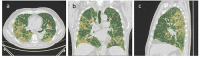

Design and methods: We enrolled a cohort of 115 patients affected by Covid-19, who performed a chest CT scan in the Emergency Department and a chest CT 18 months after hospital discharge. We performed a comparison between chest CT scan 18 months after discharge and spirometric data of patients enrolled. We obtained quantitative scores related to well-aerated parenchyma, interstitial lung disease and parenchymal consolidation. A radiologist recorded the characteristics indicated by the Fleischner Society and "fibrotic like" changes, expressed through a CT severity score ranging from 0 (no involvement) to 25 (maximum involvement).

Results: 115 patients (78 men, 37 women; mean age 60.15 years old ±12.52). On quantitative analysis, after 18 months, the volume of normal ventilated parenchyma was significantly increased (16.34 points on average ±14.54, p<0.0001). Ground-glass opacities and consolidation values tend to decrease (-9.80 and -6.67 points, p<0.0001). On semiquantitative analysis, pneumonia extension, reactive lymph nodes and crazy paving reached statistical significance (p<0.0001). The severity score decreased by 2.77 points on average (SD 4.96; p<0.0001). There were not statistically significant changes on "fibrotic-like" changes correlated with level of treatment and there was not a statistically significant correlation between CT lung score and spirometric results obtained 18 months after discharge.

Conclusions: Patients recovered from Covid-19 seem to have an improvement of ventilated parenchyma and "fibrotic-like" alterations. The level of treatment does not appear to influence fibrotic changes.